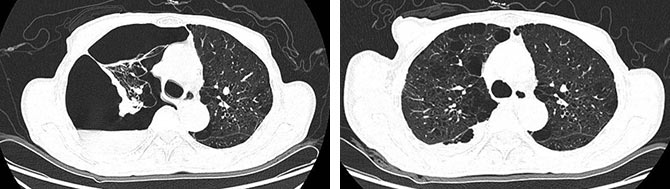

胸部CT。左:右侧液气胸,右肺受压塌陷约 90%,合并双肺多发肺气肿改变(2025-12-03)。

右:原压缩右肺较前复张(2025-12-10)